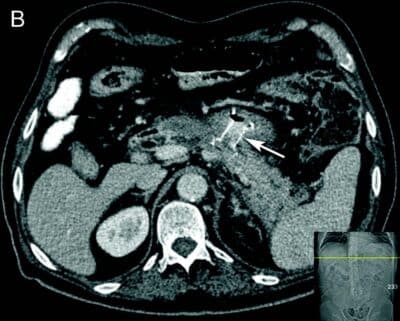

Endoskopisk behandling er som nevnt førstelinjebehandling og bør uansett forsøkes først dersom teknisk mulig da ekstern drenasje av væskefasen og eventuell tilførsel av luft i WON kan vanskeliggjøre senere endoskopisk behandling. Tilhelingstid er normalt 4-6 uker avhengig av størrelse, utbredelse og andel faste nekroser i kaviteten, men kan hos enkelte pasienter være betydelig lenger. Stenten (LAMS) fjernes når kaviteten er borte (Fig 2).

- Fig 2: CT bilder fra pasient med nekrotiserende pankreatitt og behandlingstrengende WON før drenasje (A) og 4 uker etter (B) innleggelse av LAMS (pil).